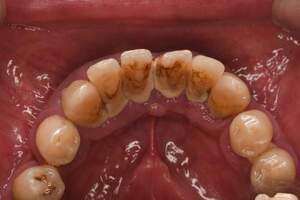

※40代・男性:歯科医院は久しぶりに受診。セルフケアがうまくできていなかった患者さま

歯の裏側の唾液の出口から出た唾液と、歯垢が結合し、石灰化を起こしてできる歯石で、黄色っぽい白色をしています。舌で歯を触ってみて、ざらざらしている部分が歯石です。

歯の表面などにでき、簡単に取れる硬さのため、すぐに除去することが可能です。歯肉縁上歯石は、歯肉炎の原因にもなります。軽度の歯周病であれば、歯肉縁上歯石の除去と、毎日のセルフケアで歯垢を取り除くことにより、症状を改善することができます。